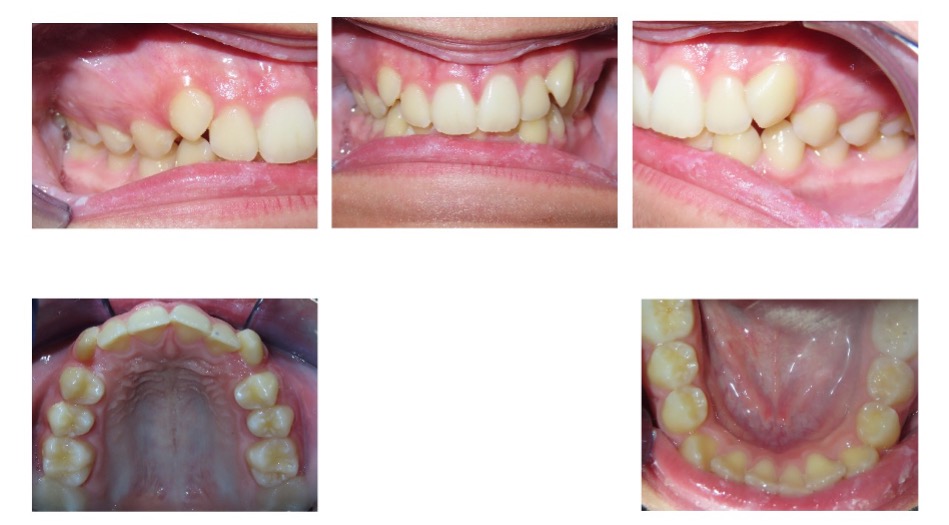

Case 4 – 14 attachments

Previous brand with typical attachment protocol (14 attachments, progress photos at 21 months)